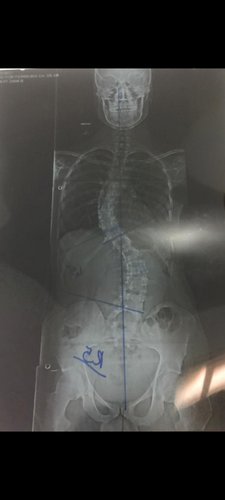

Tratamento escoliose Victor

Eu Joice, criei essa vakinha  online para ajudar nos custos, tratamento de escoliose do meu filho Victor de 18 anos.Tentei recorrer ao tratamento com o colete 4D mas no caso dele não vai solucionar.  Será necessário fazer uma cirurgia que p ver tudo

Eu Joice, criei essa vakinha  online para ajudar nos custos, tratamento de escoliose do meu filho Victor de 18 anos.

Tentei recorrer ao tratamento com o colete 4D mas no caso dele não vai solucionar.

Será necessário fazer uma cirurgia que particular custa cerca de 150.000.00, estamos na fila de espera para fazer pelo SUS mas é um processo muito demorado e pode levar até 2 anos para sair a cirurgia.

Quanto mais tempo demorar para operar o quadro dele vai piorando pois a doença vai evoluindo com o passar do tempo e piorando o quadro.

Também preciso arcar com o custo de consultas médicas, psicólogo, medicamento, recuperação da cirurgia, fisioterapeuta no pós operatório.